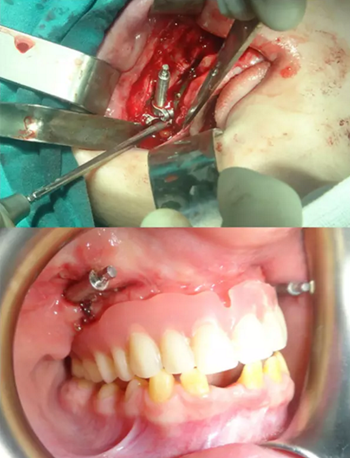

該患者的治療目標(biāo)是恢復(fù)牙頜面的正常功能和美觀,包括頜骨的垂直關(guān)系及咬合關(guān)系。治療步驟分別是術(shù)前診斷,制備引導(dǎo)性義齒,外科手術(shù)(Le FortⅠ型截骨牽張成骨),種植體植入及最終的義齒修復(fù)。上頜牽張 10 天(每天 0.5 mm×2 次),二期拆除牽張器并行種植體植入,術(shù)后出現(xiàn)輕微的感覺(jué)異常及開(kāi)口困難,癥狀于 2 周后緩解。經(jīng)頭影測(cè)量可見(jiàn) A 點(diǎn)、ANS 點(diǎn)、上唇、鼻尖點(diǎn)分別前移 6 mm、 8 mm、5 mm、2 mm。最后行義齒修復(fù)上頜牙列缺失?;颊邔?duì)最終的美觀及功能恢復(fù)感到滿意。

圖 6. 安放牽張器及義齒引導(dǎo)